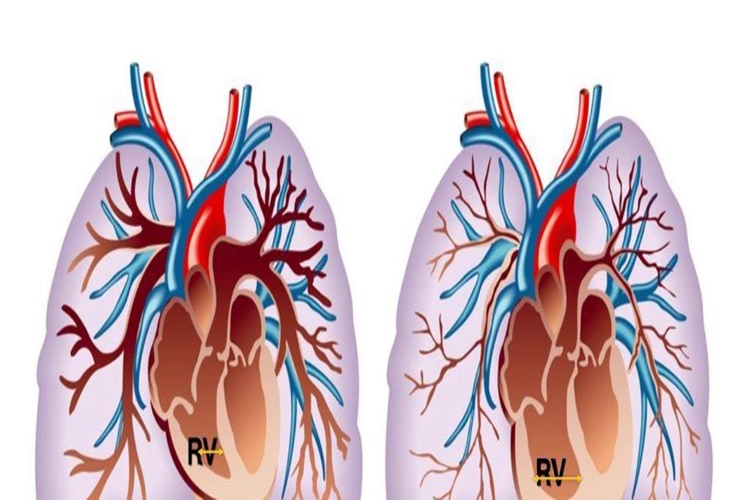

Medikal Ürünleri Devlet Karşılıyor Mu?

Medikal ürünlerin devlet tarafından karşılanıp

karşılanmadığı ülkeye, sağlık sistemine ve ilgili sağlık politikalarına bağlı

olarak değişebilir. Birçok ülkede devlet sağlık sistemi, temel tıbbi hizmetleri

ve ilaçları karşılar, ancak bazı özel veya ekstra medikal ürünler için bu

geçerli olmayabilir.

Özel bir medikal ürünün devlet tarafından karşılanıp

karşılanmadığını öğrenmek için yerel sağlık otoriteleri, sağlık sigortası kuruluşları

veya medikal ürünlerin satıldığı eczanelerle iletişime geçmeniz gerekebilir.

Medikal ürünlerin karşılanma durumu, ürünün tıbbi gerekliliklere ve tedavi

planına uygunluğuna, hastanın sağlık durumuna ve sigorta veya kamu sağlık

hizmetleri politikalarına bağlı olarak değişebilir.

Dolayısıyla, belirli bir medikal ürünün devlet tarafından

karşılanıp karşılanmadığını öğrenmek için yerel kaynaklardan güncel bilgi

almanız önemlidir.